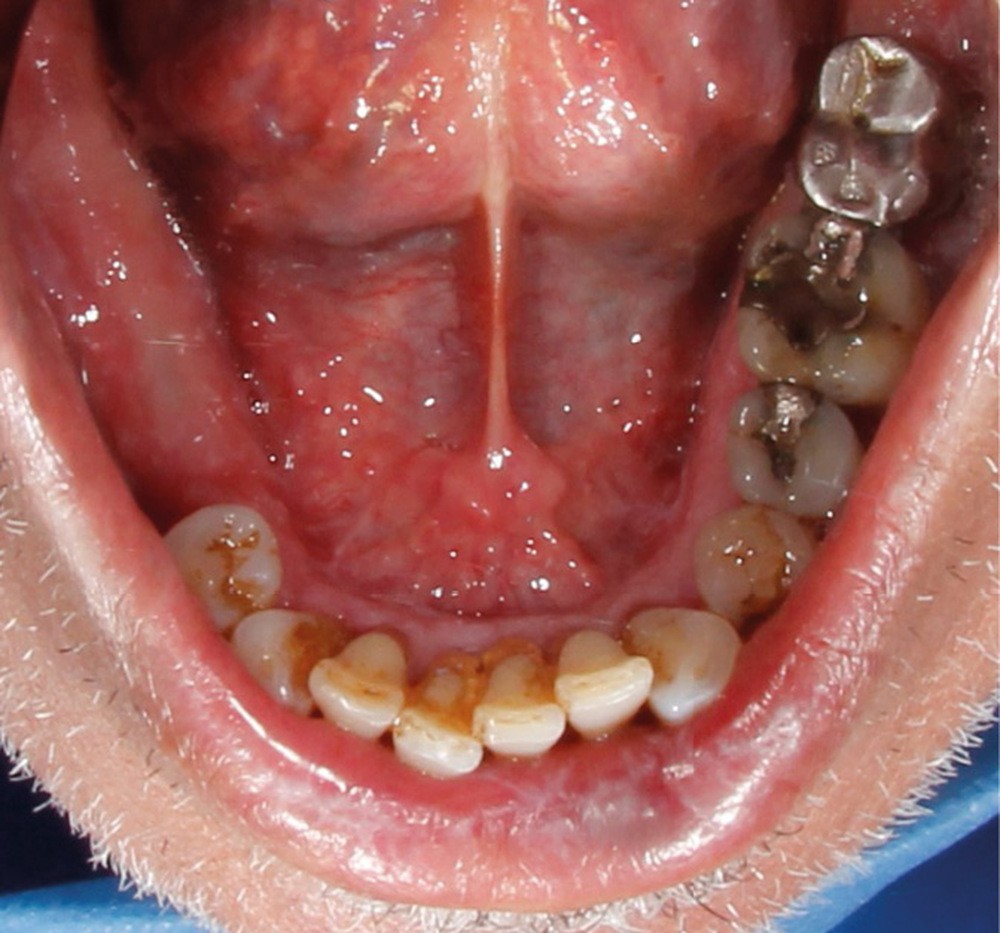

À l’interrogatoire, le patient affirme qu’il a des difficultés à maintenir une hygiène bucco-dentaire satisfaisante du fait des douleurs, et n’a pas pu consulter son chirurgien-dentiste pour son détartrage annuel en raison de la crise sanitaire en cours. L’examen clinique révèle une parodontite chronique (stade 3) généralisée et des lésions jugales (fig. 1 et 2), labiales (fig. 3) et gingivales (fig. 4) érythémateuses et kératosiques. Les lésions kératosiques jugales sont de type réticulé (fig. 1 et 2) ; les lésions kératosiques labiales sont associées à de petites érosions (fig. 3) ; les lésions palatines à des ulcérations (fig. 5). La langue présente une lésion blanche en « tache de bougie » (fig. 6) ; la muqueuse du plancher buccale est saine (fig. 7). Le signe de la pince est négatif. Le patient n’est pas porteur de prothèse dentaire malgré un édentement de moyenne étendue. Aucune lésion cutanée ou génitale n’est rapportée par le patient.

Le diagnostic le plus probable est le lichen plan (LP). On note, au niveau jugal, une kératinisation en réseau marquée par les stries de Wickman. Un phénomène de Koebner (exacerbation…